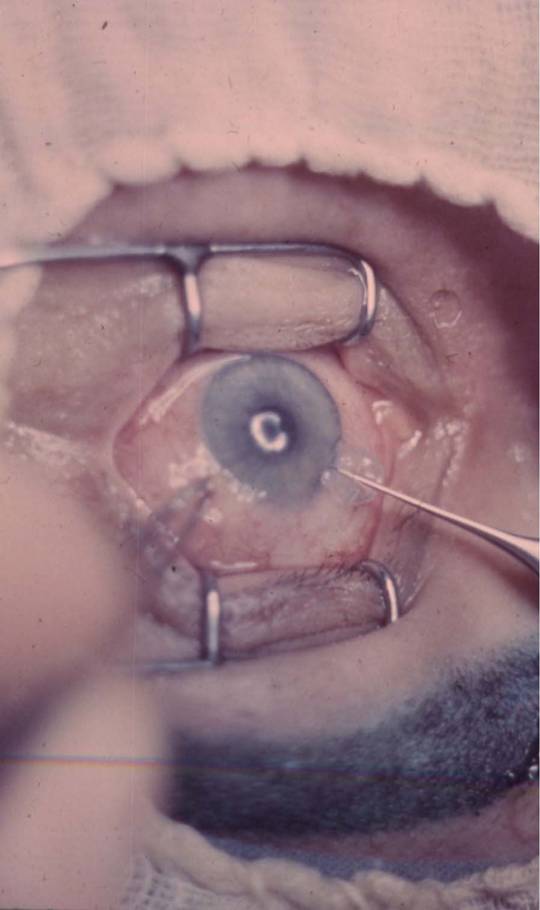

рис. 9.2.8), отмечая инъекционной иглой, смоченной 1% спиртовым раствором бриллиантовой зелени (см. рис. 9.2.9). Специальным отметчиком отмечают оптическую зону диаметром 6,0 мм (см. рис. 9.2.10). Сильный и слабый меридианы рефракции роговицы отмечают в области лимба перед подачей больного в операционную 1% спиртовым раствором бриллиантовой зелени по системе «Табо».С помощью отметчика роговицы (рис. 11.2.1) отмечают главные меридианы роговицы, затем определяют сектор сильного меридиана при простом миопическом астигматизме и по линии отметки оптической зоны производят насечку длиной до 1,0 мм на глубину 0,2 мм алмазным ножом с дозированной подачей лезвия, такую же насечку делают и в противоположном секторе (рис. 11.2.2) На глубине насечки специальным роговичным шпателем (рис. 11.2.3) делают расслаивание роговицы по линии отметки центральной зоны на % ее окружности. Точно такое же расслаивание проводят и в противоположном секторе. В сформированные тоннели микропинцетом вводят приготовленные заранее лентовидные трансплантаты с несколько заостренными краями и расправляют микрошпателем (рис. 11.2.4). Подсушенные трансплантаты имеют упругую консистенцию и легко вводятся в тоннели (рис. 11.2.5).

Рис. 11.2.2. Насечка роговицы по линии отметки оптическои зоны